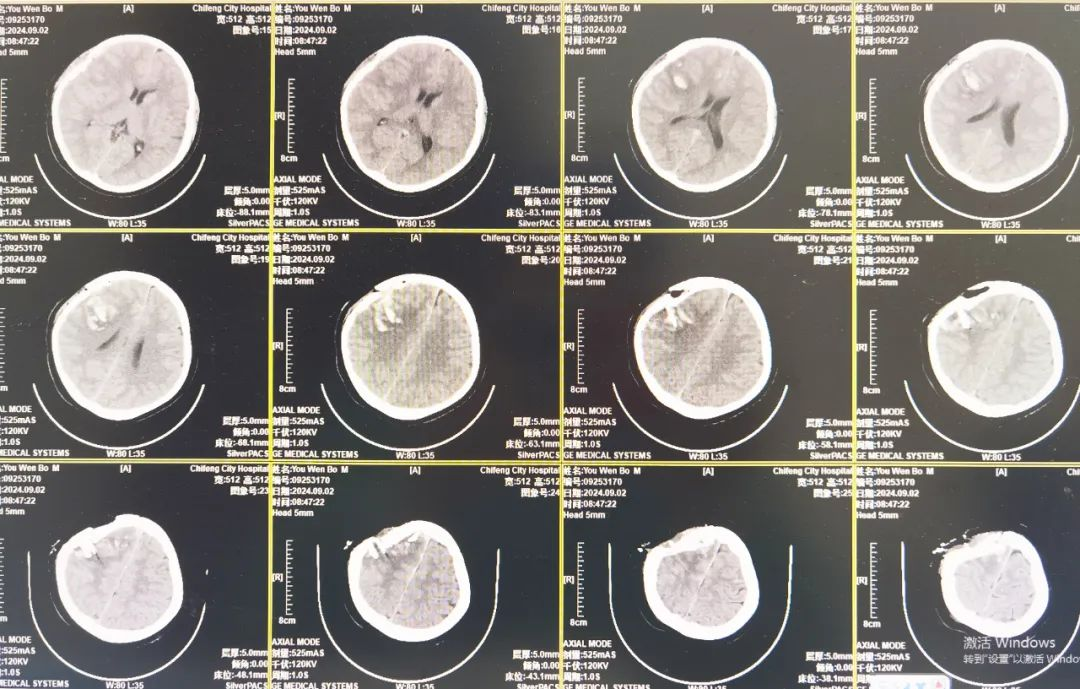

术前CT

神经外科副主任医师季明接到病情讯息后,第一时间奔向急诊重症监护病房。经分析研讨,季明医生认为患儿存在急性开放性颅脑损伤,脑组织外溢,若不手术无法存活,且术中清创不彻底会导致未来生活质量严重下降。患儿创面重度污染,骨折片嵌插颅内,骨折范围宽泛,由额顶经颞部直至同侧颅底,边缘靠近矢状窦。

术后CT

术后第二日复查头部CT,创面骨折碎片完整取出,破碎脑组织完整清除,脑组织恢复良好。患儿头部切口清洁、干燥,神志恢复,已能配合活动。